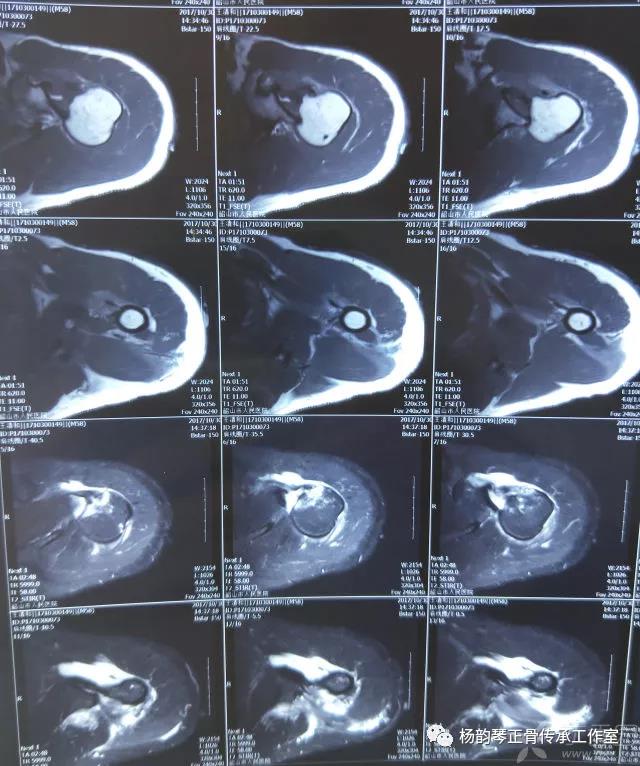

磁共振检查也完善了,还是报了个肩关节半脱位……影像科已经把坑挖好了……

接诊医生直接跳坑里了